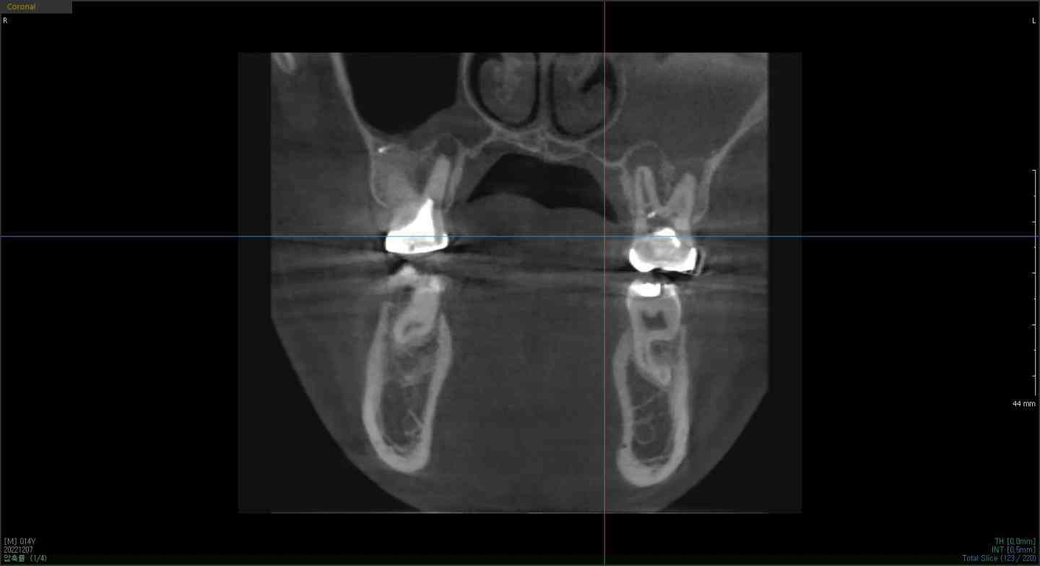

안녕하세요 저는 만성 복합치주염? 그것 때문에 윗쪽 어금니에 신경치료를 하는데 신경관을 3개중 1 개 밖에 찾지 못해 1개만 치료를 한 상태입니다. 어제 (2022-12-9) 일날 저녁에 신경치료를 마쳤는데 마취가 풀리기 전까진 괜찮았는데 다음날인 오늘(2022-12-10) 치아가 너무 아프더라고요 진통제도 먹어봤지만 그래도 아프네요. 제가 첨부한 사진은 제가 치료 전 찍은 사진이고 사진에서는 제 어금니와 잇몸을 보여주고 있습니다. 왼쪽 어금니의 잇몸을 보시면 검은색으로 텅 비어있습니다. 하지만 오른쪽 어금니의 잇몸 부분에는 회색으로 염증? 같은게 차 있다고 합니다. 어쨌든, 신경치료 후 치통이 있다는 건 인터넷에서 봤지만 제가 복용중인 소염 진통제로는 통증이 나아지질 않네요 어떻게 하면 좋을까요?

치아 뿌리끝에 염증이 많이 잇는거 같습니다. 염증때문에 통증이 아직잇으신거 같은데 일단 진통제를 드시고 치과에 가셔서 염증약을 처방받아서 드시는게 좋을것같습니다.